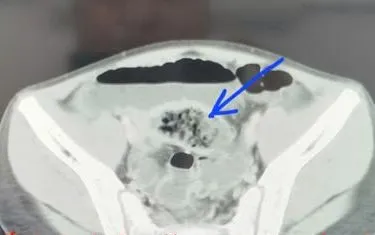

Bệnh nhi V.Q.A. (11 tuổi, phường Lê Ích Mộc, Hải Phòng) nhập viện tại Bệnh viện Nhi Hải Phòng trong tình trạng đau bụng cơn, kèm nôn. Sau thăm khám và xét nghiệm, bác sĩ chẩn đoán tắc ruột do bã thức ăn và chỉ định phẫu thuật nội soi.